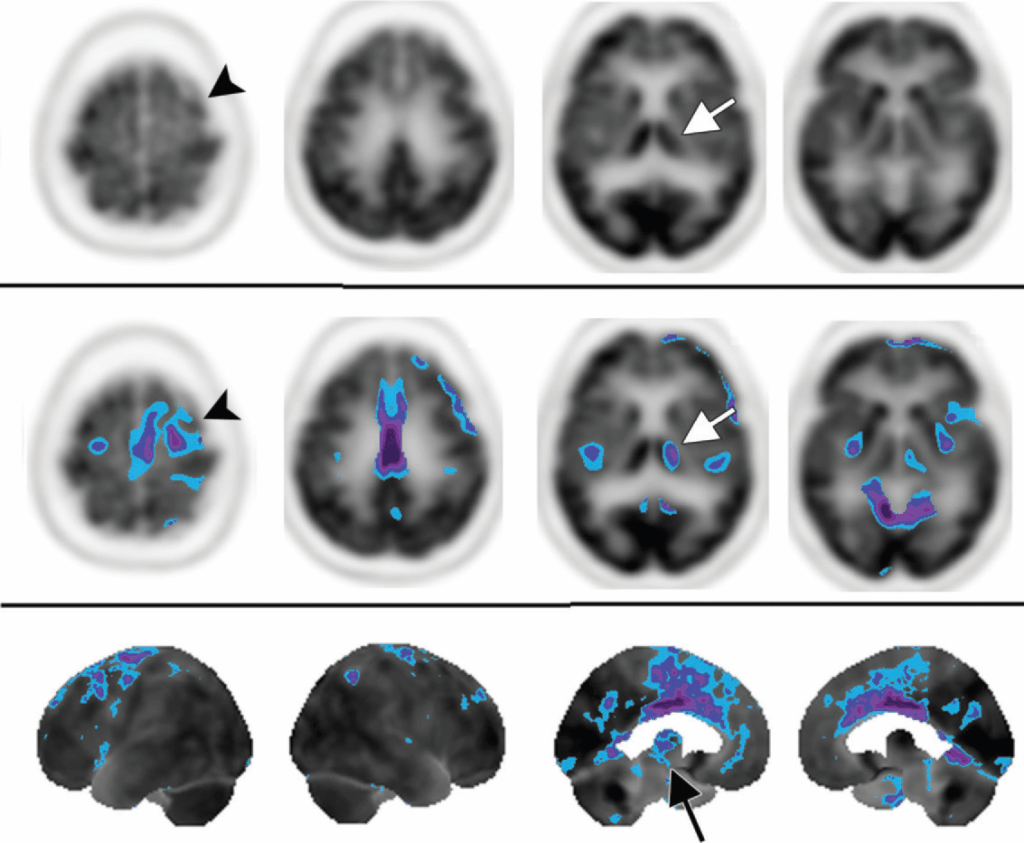

Durante la valutazione di un esame per sospetta demenza, è cruciale identificare e analizzare attivamente due strutture anatomiche chiave: il giro del cingolo e il precuneo. Queste aree, meglio apprezzabili sulle immagini sagittali delle superfici mediali degli emisferi, sono spesso coinvolte precocemente in molte patologie neurodegenerative.

(a) il disegno (vista parasagittale) mostra la posizione del giro cingolato (sia delle cortecce cingolate anteriore che posteriore) in arancione e della corteccia del precuneo in blu. Il precuneo è delimitato anteriormente dal ramo marginale del solco cingolato e posteriormente dal solco parieto-occipitale.

(b) L’immagine renderizzata in superficie mostra ipometabolismo da FDG nelle cortecce cingolata posteriore e del precuneo. Blu = −2 deviazioni standard, viola = −3 deviazioni standard. Il giro cingolato e il precuneo sono strutture importanti da identificare e analizzare durante la revisione delle immagini PET cerebrali con FDG ottenute in pazienti con compromissione cognitiva.